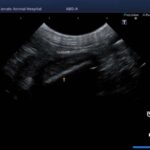

頻繁に嘔吐・下痢をするワンちゃんの精密検査依頼で内視鏡検査のご紹介がありました。内視鏡検査で上部・下部消化管を検査し、粘膜を採取し病理組織検査に出しました。結果は「胃:らせん菌感染を伴う慢性胃炎(中程度)/結腸:慢性腸炎(軽度)」とのことでした。その後かかりつけの先生のところ […]